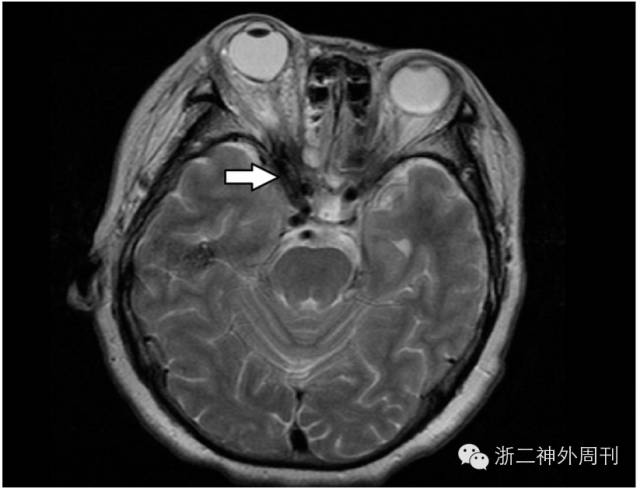

术后头颅MRI检查见右侧眼眶深部混杂信号,放射科报告考虑:1.窦道血肿;2.眶壁肿胀组织;3.不排除少量异物残留可能(图5)。考虑再手术探查的难度及风险,与家属沟通后建议密切随访观察。患者经抗炎治疗,创口愈合可,异物拔除1周后出院。

图5. 术后MRI检查,可疑少量异物残留。